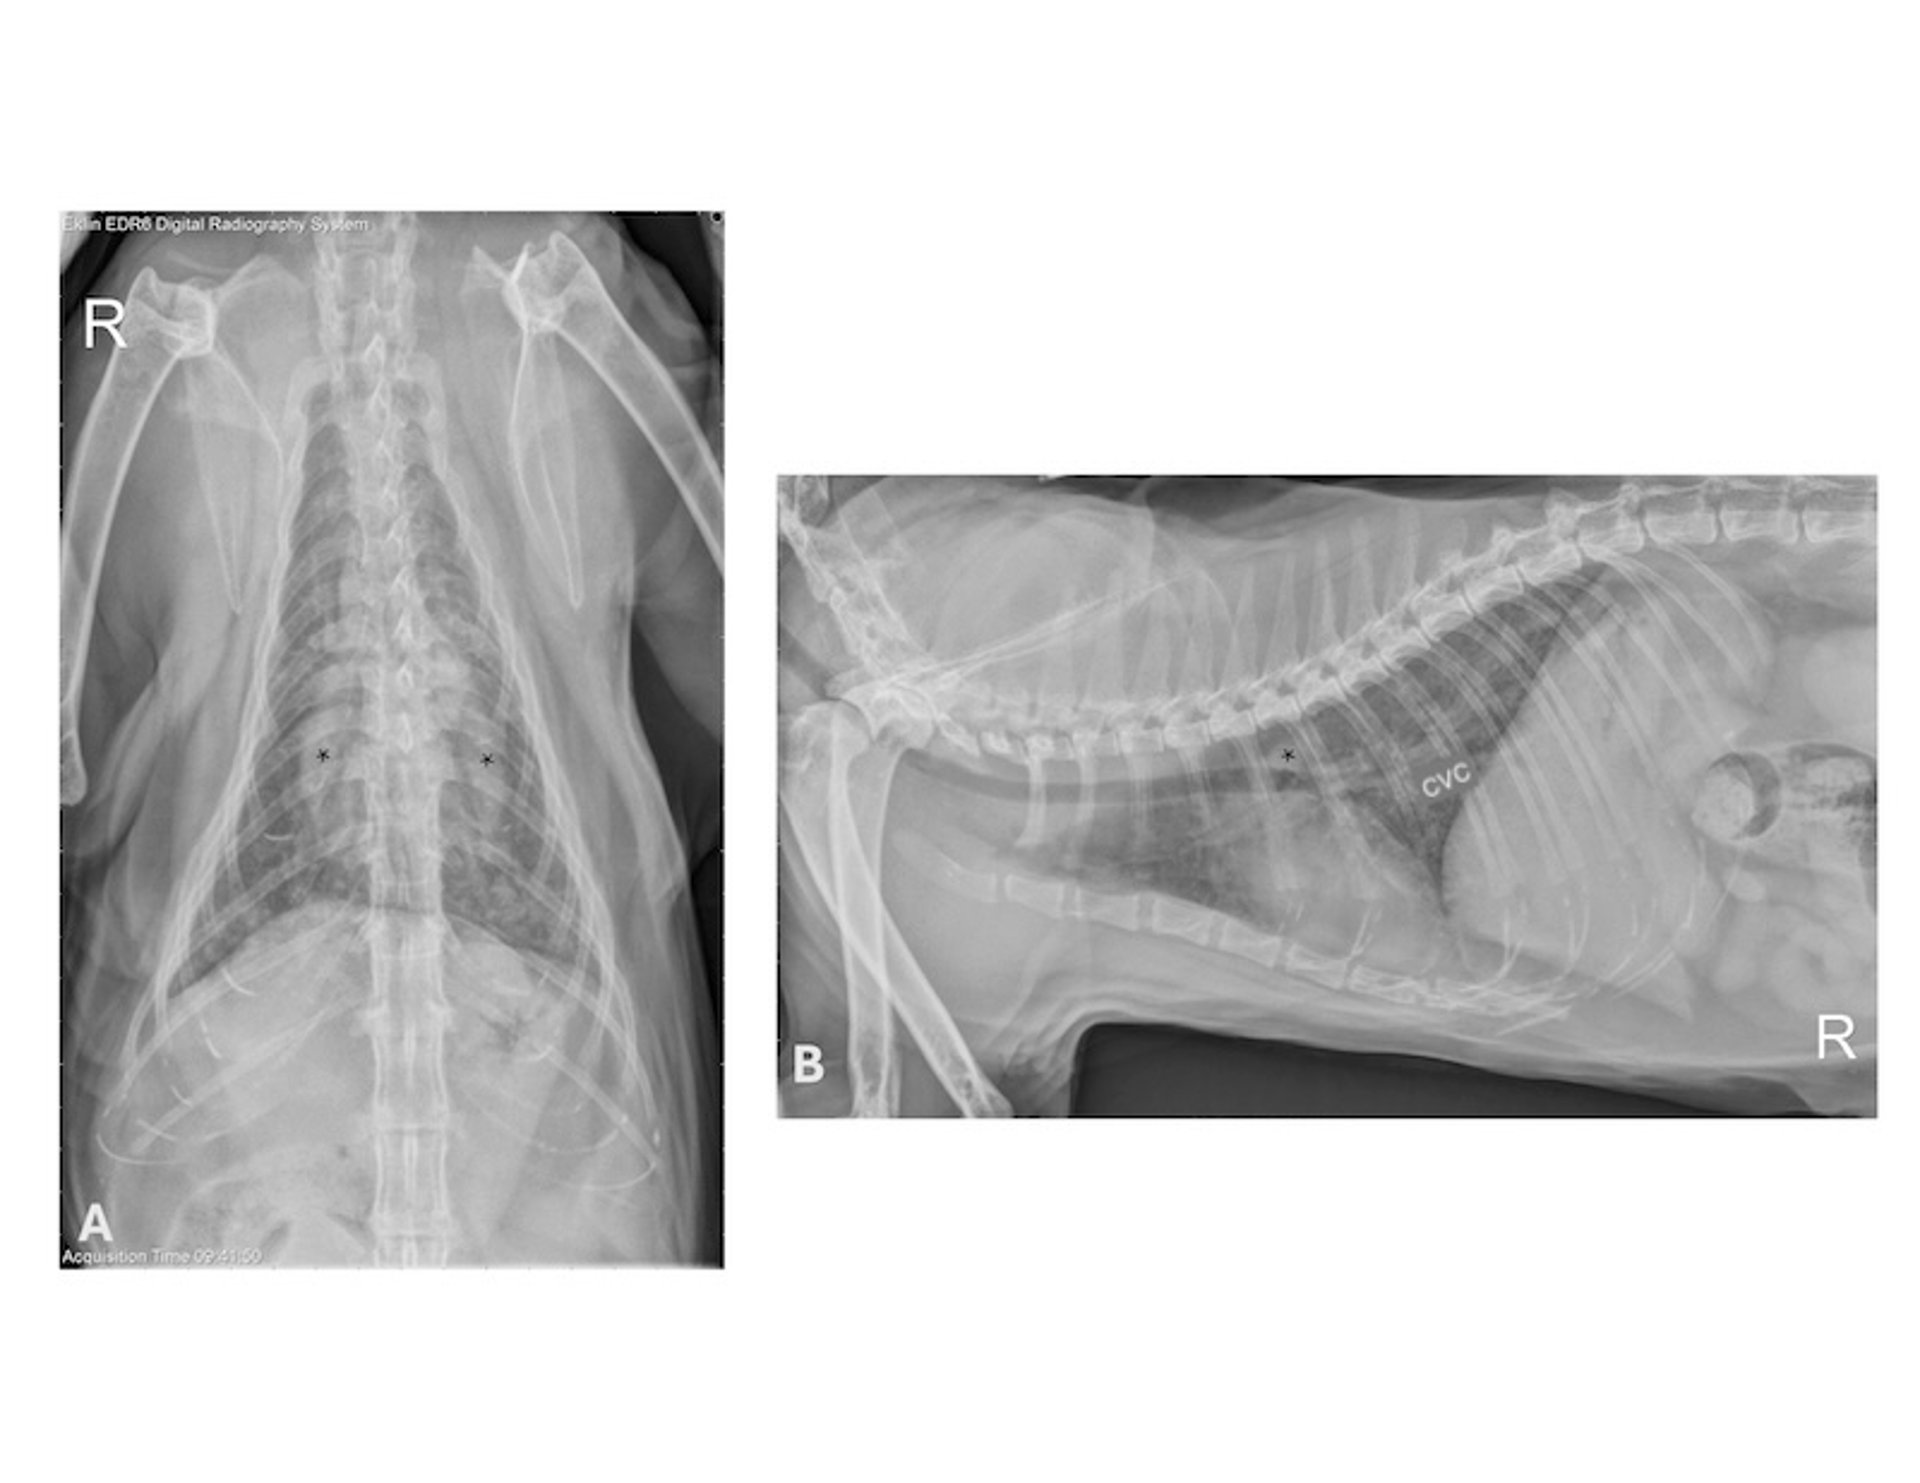

Mature heartworm infection, radiographs, cat

Ventrodorsal (A) and right lateral (B) radiographs from a 5-year-old male cat with a history of cough. Heartworm antibody and antigen test results were both positive, and worms were visualized within the main pulmonary artery on echocardiogram. Note the diffuse, bronchointerstitial pattern with a subtle nodular component. Caudal lobar pulmonary arteries are dilated and mildly tortuous (*). There is mild enlargement of the cardiac silhouette; however, wall thicknesses and chamber dimensions were normal on echocardiography. CVC, caudal vena cava.

Courtesy of Dr. Marisa K. Ames.